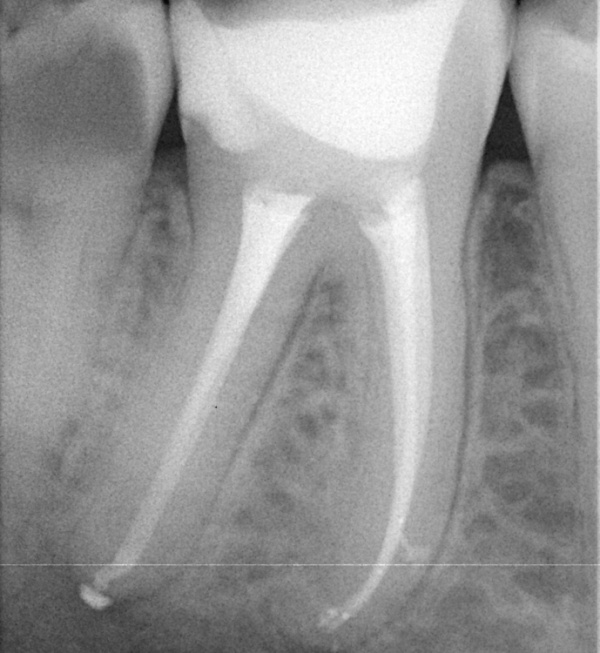

• Náročná anatomie: Praktický a srozumitelný návod, jak zvládnout komplikované kořenové kanálky – zejména typu MB2 a dolní moláry v běžné praxi. Zaměření na přístup, možné komplikace a plnění kořenových kanálků, srovnání ručních technik a strojové endodoncie.

• Opracování MB2 (Biovoxel/trepanovaný horní molár č. 16) za použití nástrojů systémů PTUL a TN.

• Zaplnění k.k..